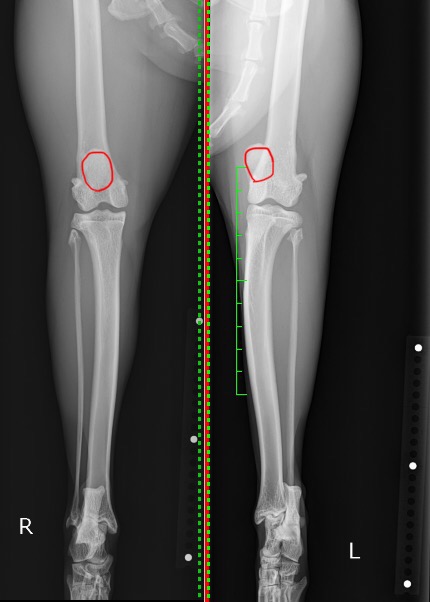

後肢を正面から撮影しているX線を見比べると、右後肢は膝蓋骨(赤丸)が大腿骨の中央に位置し滑車溝にはまっているのに対し、左後肢の膝蓋骨(赤丸)は内側に位置(内方脱臼)しているのが分かるかと思います。